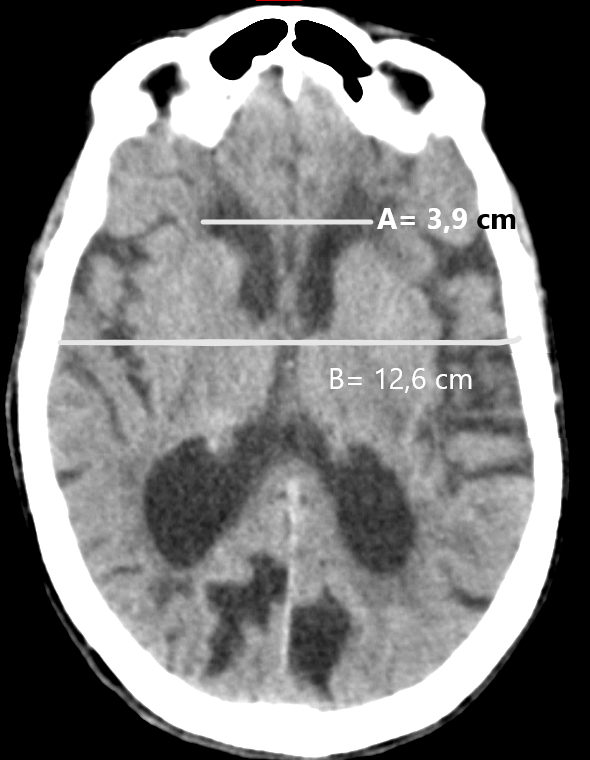

Para llevar a la práctica este método de medición del volumen de los hematomas intraparenquimatosos mediante una TC de cerebro, se elige el corte con el área de mayor sangrado, midiéndose el máximo diámetro anteroposterior del mismo (parámetro A). El parámetro B corresponde al diámetro transversal de la lesión en ese mismo corte.3,4,7 El parámetro C es el número de cortes en los que se aprecia sangrado multiplicado por el espesor de corte (►Fig. 1).1,3,4,7

La fórmula es: A x B x C /2 y el resultado final se expresa en centímetros cúbicos.1

A) Índice bicaudado: se obtiene dividiendo la distancia mínima de los ventrículos laterales a nivel de las cabezas de los núcleos caudados con el diámetro del cráneo a ese mismo nivel (►Fig. 4).

B) Índice de Evans: se calcula dividiendo el diámetro máximo de las astas frontales de los ventrículos laterales con el diámetro máximo intracraneal en el mismo corte a la altura de los forámenes de Monro (►Fig. 5).22,23,24

Un valor > a 0,30 indica ventriculomegalia y puede considerarse patológico, pero no puede discriminarse la etiología por atrofia u otra entidad.22,23,24

C) Índice bifrontal: se calcula dividiendo el diámetro máximo de las astas frontales de los ventrículos laterales y el diámetro intracraneal a ese mismo nivel (►Fig. 6).22,23,24